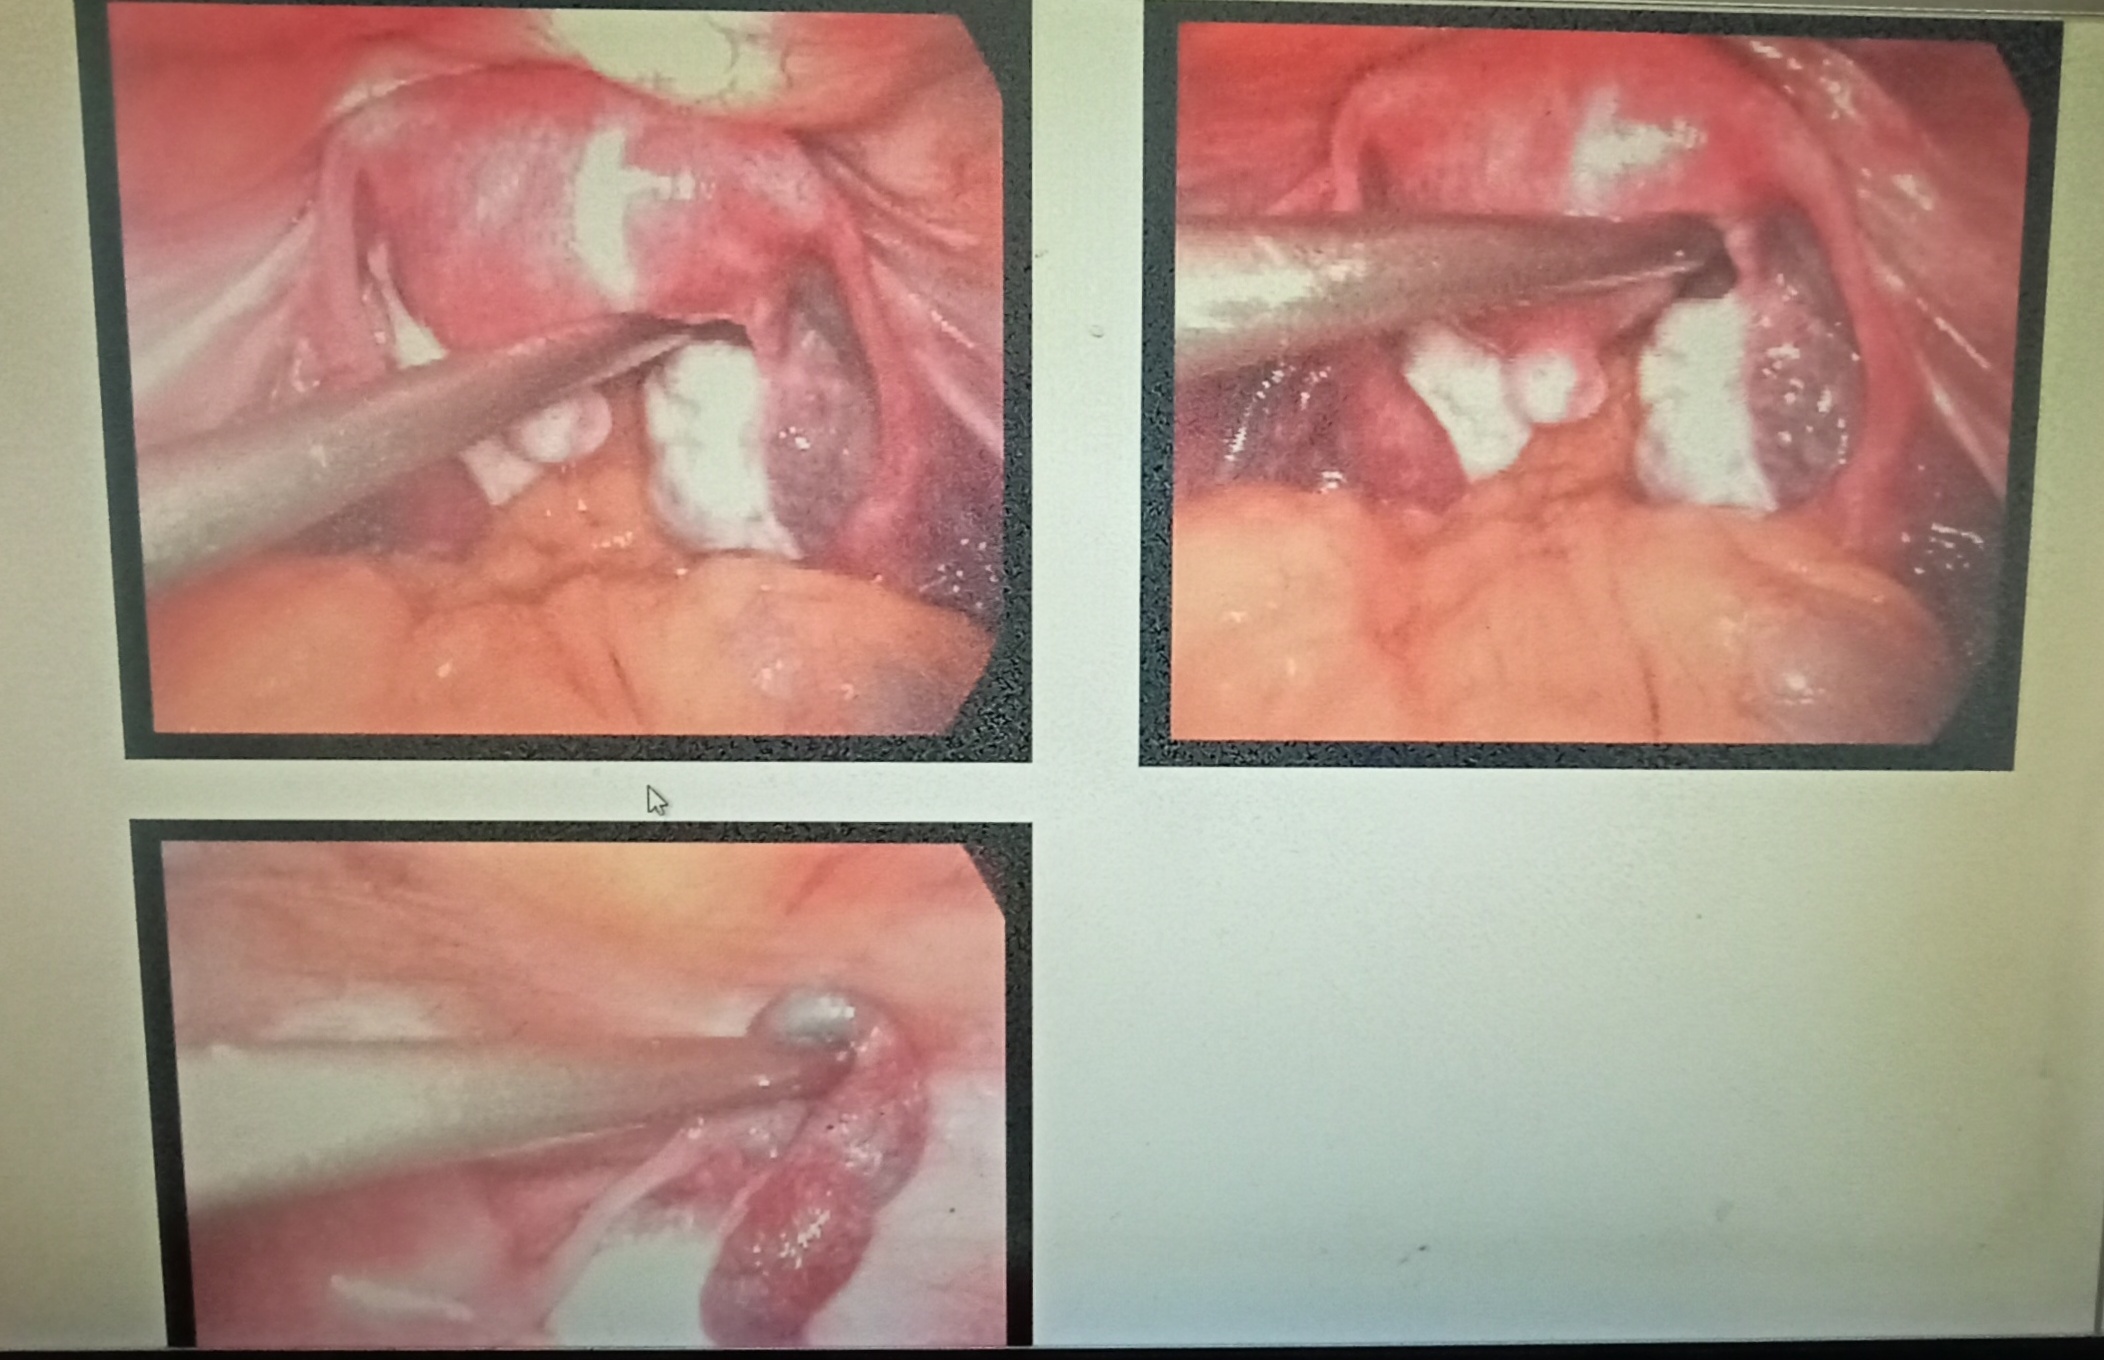

LAPRASCOPE

Laprascope done on 20th september